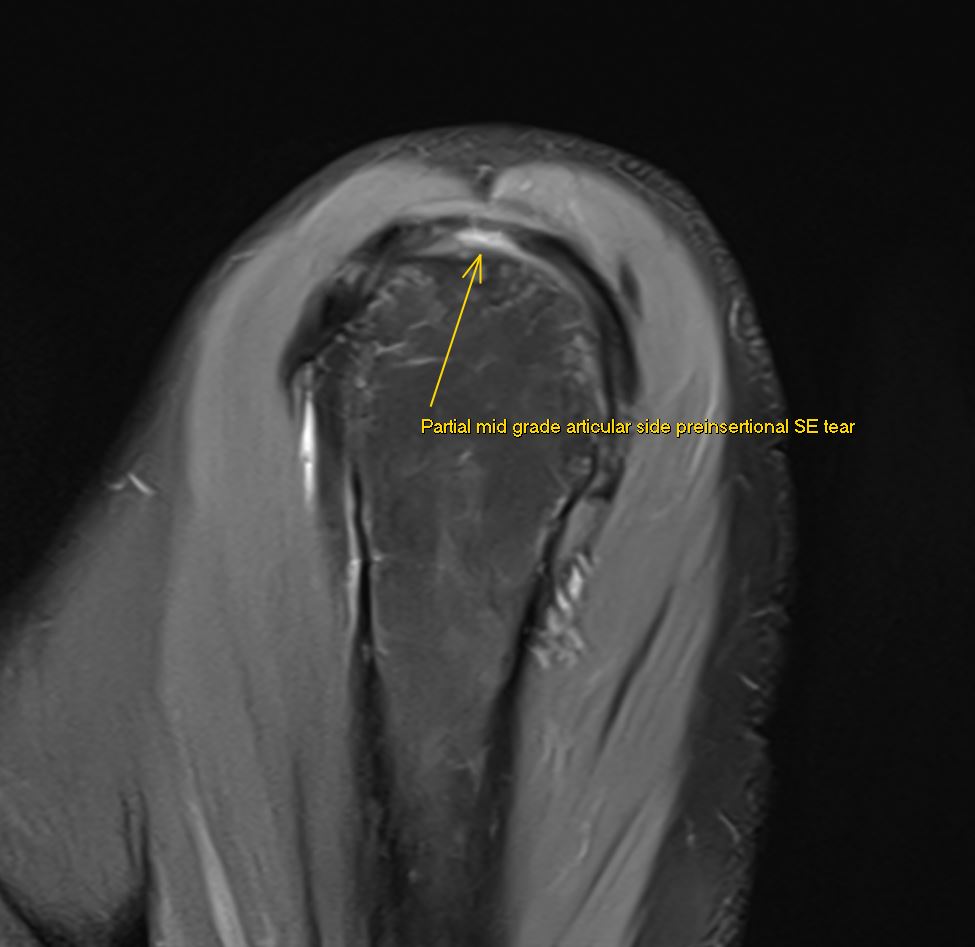

JuanMiranda@themskarchive·

5/6/2024. 👌 Thrilled to have improved MRI protocols with my teammate @pepelermarx! This #shoulder MRI clearly shows a preinsertional partial articular-sided mid-grade supraspinatus tear in three planes 💪. #MRI

JuanMiranda tweet mediaJuanMiranda tweet mediaJuanMiranda tweet media